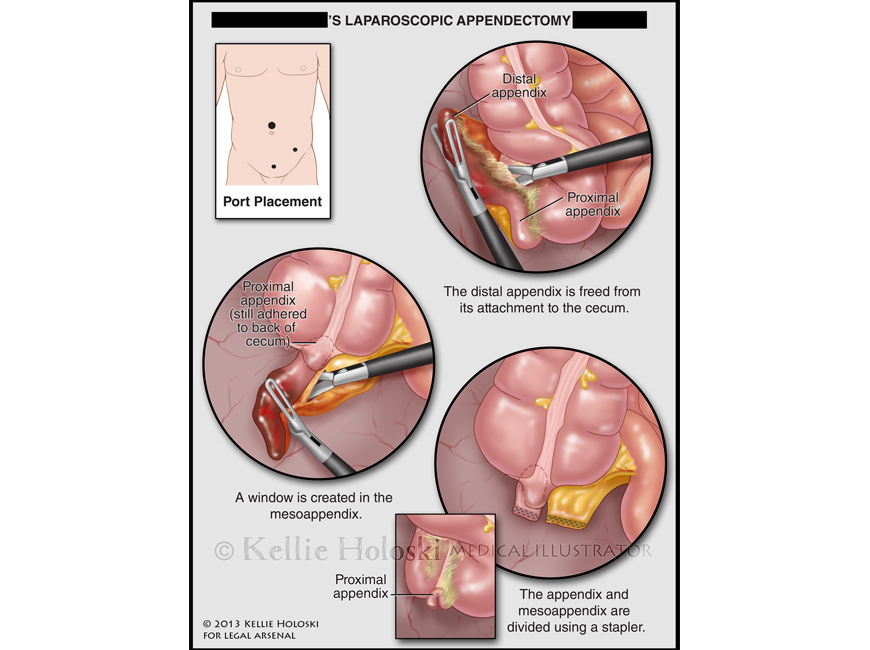

Laparoscopic Appendectomy,

Adobe Photoshop

Courtroom exhibit;

©Kellie Holoski -